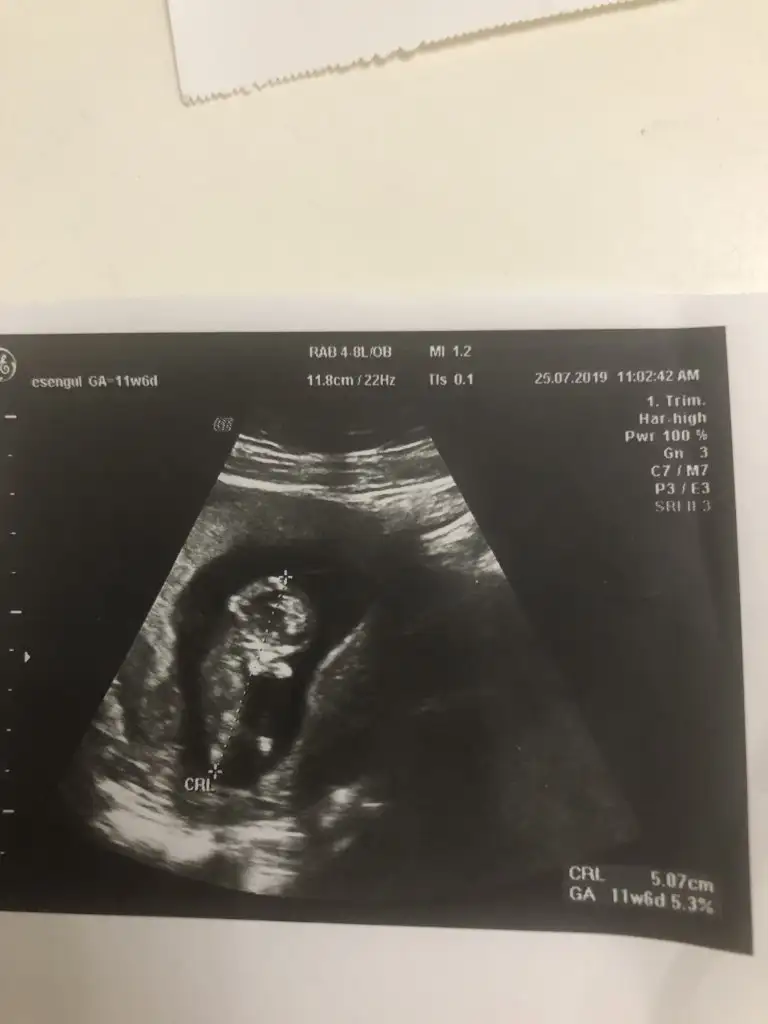

Kızlaar benim bebişede bi yorum yapsanız bende merak ediyorum cinsiyeti

Eki Görüntüle 2294674